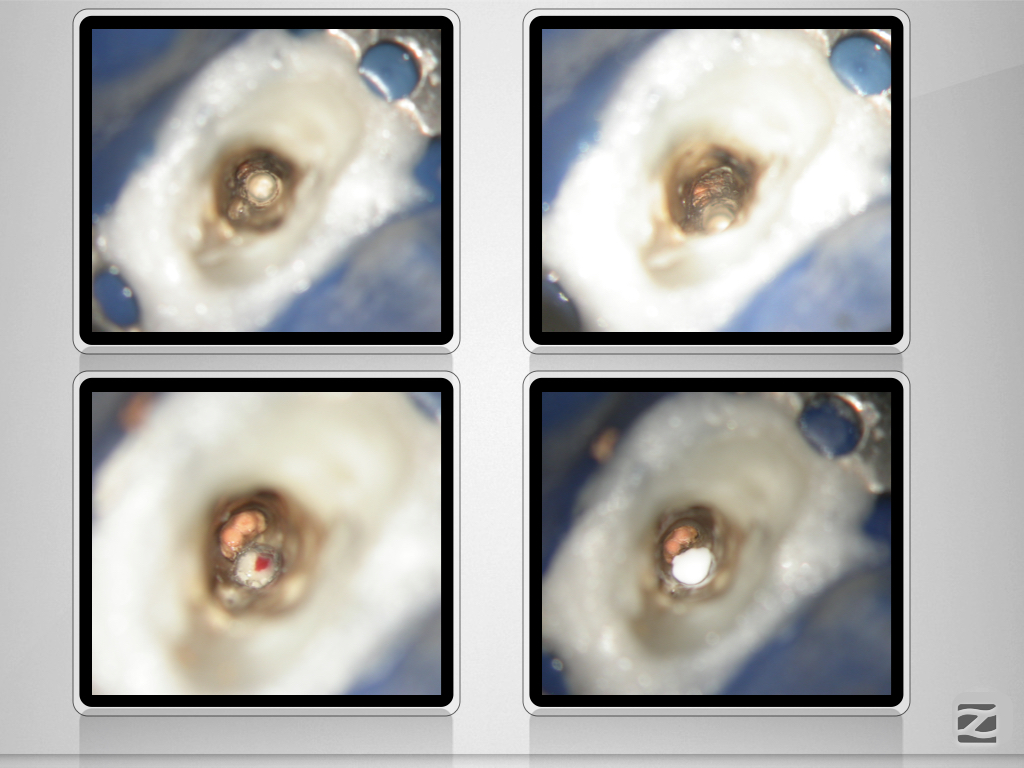

13D.009

Laterale Perforation